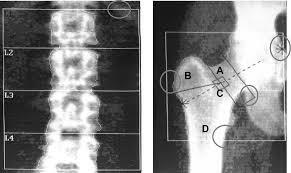

• Descubrimiento de la densitometría ósea.

Descubrimiento de la densitometría ósea.

Por J. Cameron y J. Sorenson.